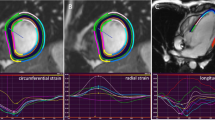

For 2D-FT MRI, the module QStrain in Medis Suite MR (version 2.1, Medis Medical Imaging Systems BV, Leiden, The Nethderlands) was used [13]. After manually setting the cine frame with smallest RV cavity area as end-systolic, the frame with largest as end-diastolic heart phase and tracing of the endo- and epicardial border in both phases, the RV was automatically divided into seven segments (Fig. 1). For each segment, peak longitudinal strain (LS, percent change in segment length from end diastole) and peak longitudinal strain rate (LSR, representing rate of myocardial deformation) were recorded (Fig. 2). The measurements were repeated twice and averaged. Global LS (GLS) and LSR (GLSR) value were calculated as the mean of all segments.

Definition of peak strain in the 2D-FT MRI and 2D-STE. During a heart cycle, peak strain can occur during a systolic (curve 1) or a post systolic (curve 2) heart phase. The peak global strain (peak G) in both imaging modalities is defined as peak strain during one heart cycle independent of heart phase. However, peak systolic strain (peak S) is defined differently in MRI and STE. In 2D-FT MRI, peak S is defined as strain at the end of systole, while in 2D-STE, it is defined as peak strain during systole. Therefore, peak S in curve 2 with postsystolic shortening is equal in both imaging modalities, while in curve 1 with peak shortening during systole peak S is different between MRI and echocardiography

To be able to compare peak strain of 2D-FT MRI and 2D-STE, peak global strain (Peak G) not peak systolic strain (Peak S) was measured. The Peak G in both imaging modalities is defined as peak strain during one heart cycle independent of heart phase. However, the Peak S is defined differently in 2D-FT MRI and 2D-STE. In 2D-FT MRI, Peak S is defined as strain at the end of systole, while in 2D-STE, it is defined as peak strain during systole (Fig. 2).

Regional and Global LS and LSR Using 2D-FT MRI and 2D-STE

Results of the regional and global LS and LSR of both imaging modalities are shown in Table 2 and Fig. 2. In 2D-FT MRI, the LS was lower in the septal segments, while LSR did not differ between the segments. In 2D-STE, the septal segments likewise showed the lowest LS and also LSR. 28% of apical segments could not be analyzed with 2D-STE due to poor image quality.

Bland-Altmann plots show that there was acceptable agreement between GLS derived by 2D-FT MRI and 2D-STE (Fig. 3), while MRI slightly undererstimates GLS. The agreement for the regional LS was not as good, being poor in the apical segments. The agreement between the two methods for LSR was poor for global, as well as for the regional segments (Fig. 4).

The wide limits of agreement in Bland-Altmann plot show that for GLSR, the agreement between 2D-FT MRI and 2D-STE was poor. Since strain rate is the time-derivative of strain, the difference in temporal resolution between the two imaging modalities might account for the poor agreement [24]. Temporal resolution in MRI can be a problem with higher heart rates in small children. In our study, median frame rate of STE was 85/s, which should be sufficient for the median heart rate of 81 bpm. In MRI, however, median number of heart phases was 25 [20–30)]. We presume that in order to detect changes in strain rate, a higher temporal resolution than 28.8 ms is required [13]. For the LV of healthy volunteers, Orwat et al. reported a poor agreement of longitudinal and circumferencial GSR between 2D-FT MRI and 2D-STE [25]. They also attributed the poor agreement to the difference in temporal resolution between the methods.